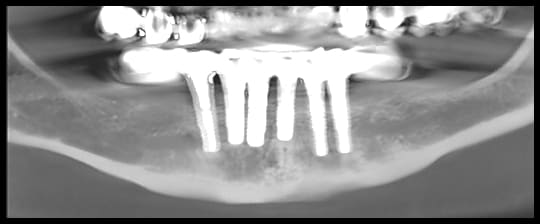

Patiente se présentant avec 6 implants posés depuis 4 ans en avant des 2 mentonniers, avec prothèse provisoire scellée suite à MCI.

Cette dernière veut réaliser une prothèse définitive mais les extensions(2 dents) étant trop importante, il y a trop de porte à faux, et le provisoire se descelle régulièrement.

Derrière il est possible de placer des implants de 4mm, les 6mm ne passent pas (crête fine).